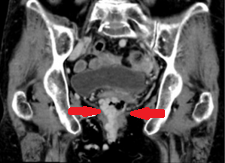

Σχήμα 2 . Σύνδρομο πυελικής συμφόρησης . Διατεταμένες αριστερές ωοθηκικές φλέβες , αριστερές ουρητηρικές φλέβες , ωοθηκικός κιρσός και παραμητρικές φλέβες . ( Ευγενική παραχώρηση Δρ Β . Πενόπουλος ) .